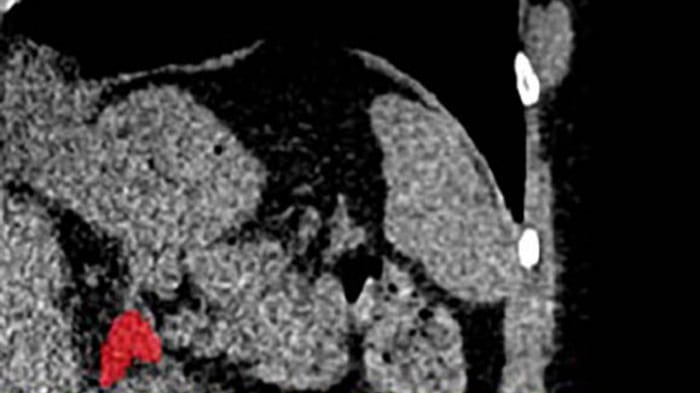

Y es que un equipo de investigadores liderado por la doctora Elena Ghotbi, del Johns Hopkins University School of Medicine, en Estados Unidos, entrenó un modelo de aprendizaje profundo para medir el volumen de las glándulas suprarrenales a partir de tomografías de tórax ya realizadas.

Dado que cada año se realizan decenas de millones de estas tomografías, la técnica tiene el potencial de aplicarse de forma masiva sin necesidad de nuevas pruebas. Gracias a este enfoque, se puede aprovechar información existente para evaluar la ‘carga biológica’ del estrés de forma objetiva.

El indicador, llamado Índice de Volumen Suprarrenal (AVI, por sus siglas en inglés), se define como el volumen de las glándulas suprarrenales dividido por la estatura al cuadrado.

Este hallazgo representa una verdadera innovación clínica: por primera vez es posible “ver” el estrés crónico acumulado en el cuerpo mediante una imagen médica habitual, en lugar de depender únicamente de cuestionarios o mediciones puntuales de cortisol.